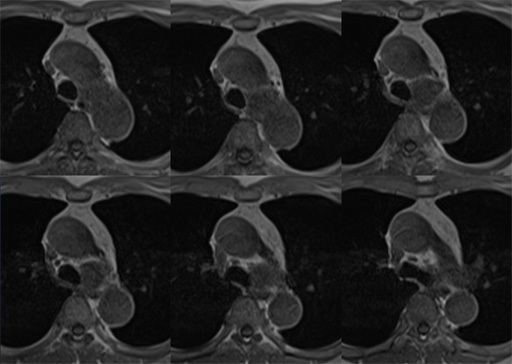

図6 胸部CT 肺野条件 図7 MRI T1WI (in phase)

図7 MRI T1WI (in phase) 図8 MRI T1WI (out of phase)

図8 MRI T1WI (out of phase) 図9 MRI T2WI